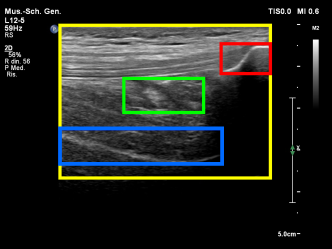

We focus on one of the three scans of the knee joint specified in HEAD-US protocol for the collection and diagnosis of joint recess distension in patients with hemophilia [7]: the SQR longitudinal scan. This scan is used to assess SQR distension and contains different characterizing elements (see Figure 1):

• The femur (blue box) usually appears as a light thick line, approximately horizontal, starting from the left side of the image and extending towards the right, often in the lower half of the image.

• The patella (red box) usually appears as a curved light line, positioned at the right border of the image, often in the top half and not entirely captured. The tendons (horizontal and parallel darker lines) can be seen on its left.

• The SQR (green box) often contains at least a small quantity of liquid and hence it is dark. In some cases, the joint recess membrane can be visible in grey. The joint recess is positioned between the femur and the patella. Its size and shape vary depending on many factors including whether it is distended or not, as explained below.

Figure 1b shows how the probe must be positioned during the acquisition of the SQR longitudinal scan. In the figure, the yellow box is the area that is captured by the US image shown in Figure 1a, while the green box is the SQR. To correctly acquire this type of image, the knee has to be bent at 30. The probe must be positioned right at the beginning of the patella and moved horizontally to identify the correct key features previously described.